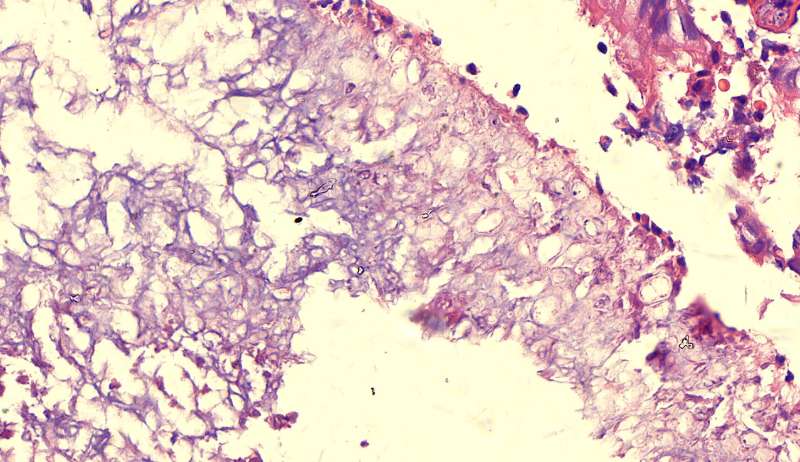

第二例隐球菌

整体是个类圆形,边界模糊(有晕征的感觉),肉芽肿一般都这样 里面也能见到许多小白球,大小从3微米到20微米不等 红细胞直径5-6微米 普通小淋巴细胞直径5微米 这里淋巴细胞挺多 有许多淋巴细胞,成堆

多核巨噬细胞吞了许多隐球菌 经常是反包围的感觉

这三幅是周围区,也有巨噬细胞,单核的多 都在肺泡腔内 所以有ggo样密度 过一段时间,晕就消失,有时是消退,有时是实性区扩大,盖住磨玻璃晕 那也是吞噬的作用,常代表免疫力正常 就是警察多了把肺泡填了

前两幅是第一例

第二例也是类圆形结节状

第三例

许多小白球--隐球菌,不做PAS及六铵银特染也看得清 荚膜的感觉明显 第三例的CT